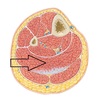

What are the 4 layers of the plantar aponeurosis?

Short intrinsic muscles

Long tendons

Short muscles

Interossei muscles